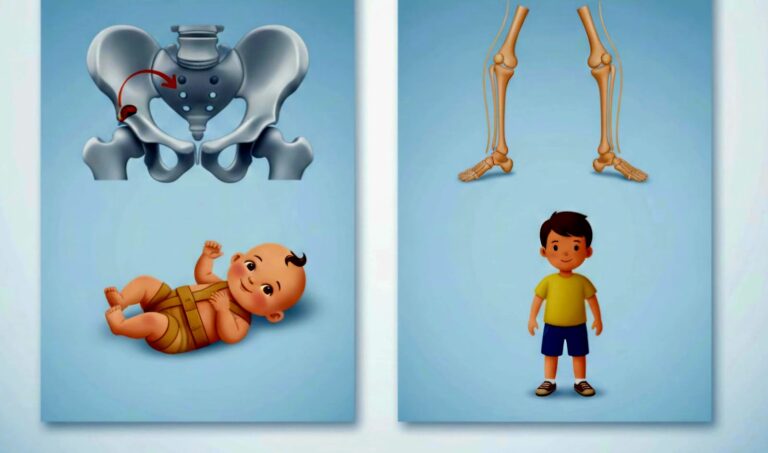

مقدمة: عظام الأطفال مرنة، لكن بعض العيوب قد تظهر منذ الولادة أو مع بداية المشي وتؤثر على مستقبل الطفل الحركي. أولاً: خلع الورك الولادي (DDH) يحدث عندما لا يكون رأس الفخذ مستقراً داخل الحوض. الاكتشاف المبكر في أول شهرين يعني…